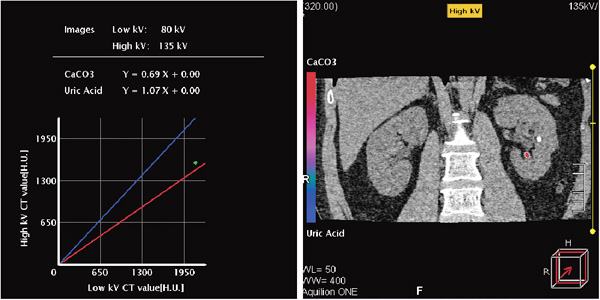

解析結果は図5のように,グラフとカラーコーディングにより表示される。左側のグラフは,横軸が低管電圧,縦軸が高管電圧のCT値であり,(2)で選択した部分のCT値を確認することができる。赤と青の線は,あらかじめ設定された2つの物質がグラフ上で取りうるCT値を示しており,図5では,青が尿酸,赤が炭酸カルシウムから得られた値である。このグラフの上に,選択した部分に相当する点がプロットされる。図5の場合は,赤い線の近くに点がプロットされ,炭酸カルシウムに近いことが示唆される。右の画像には,選択した部分がどちらの物質に近いかが,グラフとカラーコーディングにより示される。色使いはグラフと同じで,青が尿酸,赤が炭酸カルシウムであり,(2)で選択した部分の計測結果から,赤く表示されている。このようにして,選択した部分のCT値を,基準となる物質のCT値と比較しながら確認することができる。

図5 解析画面例